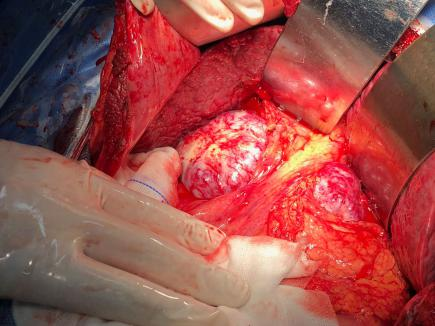

如解剖性精准肝叶、肝段切除,胰十二指肠切除,全胰腺切除,肝门部胆管癌根治(围肝门切除),胆管损伤修复,门脉高压断流、分流等。以下是部分手术图片。

二、胰腺手术

1.胰十二指肠切除